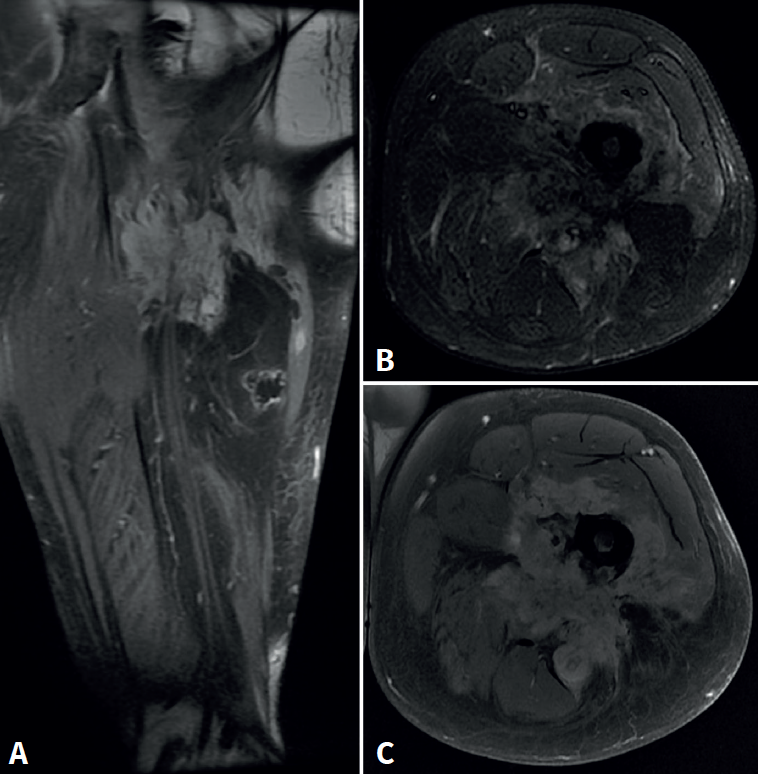

retla.08216.fs2508016-figura4.png

Figura 4. Resonancia magnética del fémur izquierdo. A: corte coronal en secuencia STIR, con masa de partes blandas de gran tamaño con afectación diafisaria femoral; B: corte axial en secuencia T2, con masa heterogénea con áreas de necrosis central; C: corte axial en secuencia T1 con supresión grasa, con compromiso del trayecto del nervio ciático por la masa tumoral.